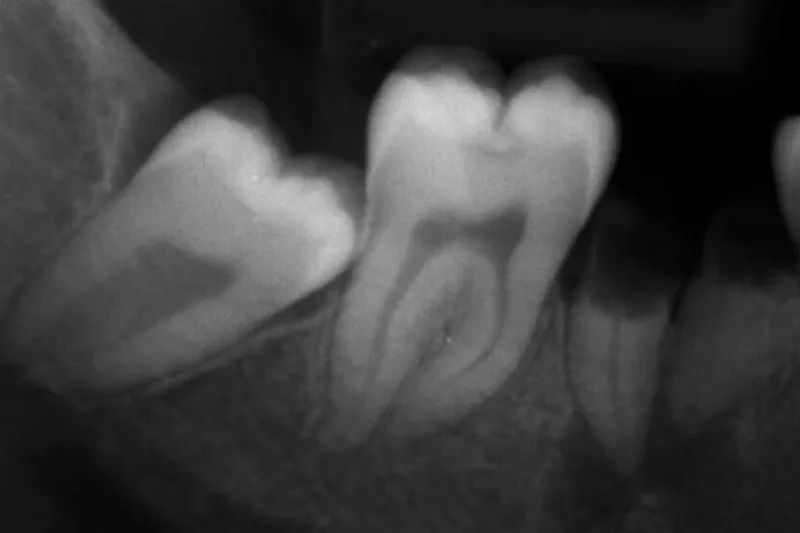

En ung asylansøger dukker op uden identifikationspapirer, og det er afgørende for den videre sagsbehandling at få oplyst, om personen er over eller under 18 år. Dette kræver en retsmedicinsk undersøgelse, og et vigtigt led heri er vurdering af visdomstændernes udviklingsstadie.

Undersøgelsen er baseret på vurdering af panoramaoptagelser fra 1.302 personer (ca. 50 af hvert køn i hver aldersgruppe fra 13 til 25 år). I alt blev 5.158 visdomstænder vurderet. 100 optagelser blev undersøgt flere gange med henblik på bestemmelse af registreringernes reproducerbarhed. Udviklingsstadiet blev registreret på en skala fra 1 til 10, hvor 10 repræsenterer en færdigdannet tand.

Resultaterne viste, at visdomstænderne udvikles hurtigere i overkæben end i underkæben, at udviklingen sker hurtigere hos mænd end hos kvinder, og at den mesiale rod på underkæbevisdomstænderne udvikles hurtigere end den distale. Der var høj grad af overensstemmelse mellem registreringerne, både når de blev foretaget af to forskellige undersøgere, og når den samme undersøger registrerede ved to forskellige lejligheder (kappa-værdier 0,86-0,95).

Visdomstænderne udvikles hurtigere i overkæben end i underkæben, og udviklingen sker hurtigere hos mænd end hos kvinder